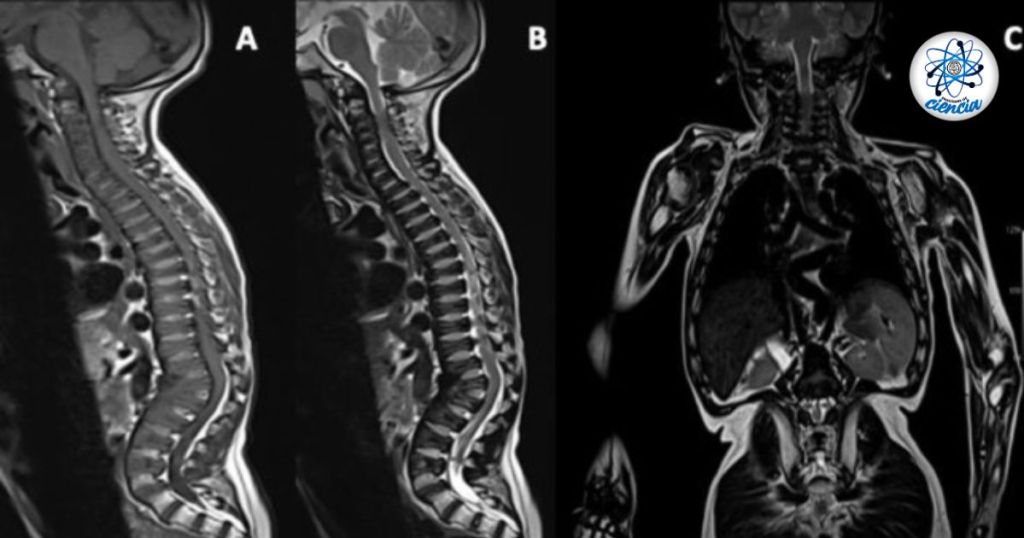

La Mucopolisacaridosis, más conocida como el Síndrome de Morquio, es <<una enfermedad rara en la cual el cuerpo no tiene suficiente cantidad de una enzima necesaria para descomponer cadenas largas de moléculas de azúcar>> de acuerdo con la Biblioteca Nacional de Medicina.

Existen varios tipos de enfermedades que pertenecen al mismo grupo; mucopolisacaridosis, y de la que te hablamos hoy es la MPS IV, sin embargo, también está MPS I o síndrome de Hunler, MPS II o síndrome de Hunter y MPS III o síndrome de Sanfilippo.

Entre las señales más inequívocas de este síndrome encontramos el desarrollo anormal en huesos, ccostillas ‘ensanchadas’ del inferior, rasgos faciales más gruesos.

Sin embargo, también pueden aparecer gernias en la ingle, dientes abiertos o espaciados, piernas en forma de ‘X’.

Y, en cuestiones más delicadas un soplo cardiaco, cabeza grande o macrocefalia, estatura más baja de lo normal.